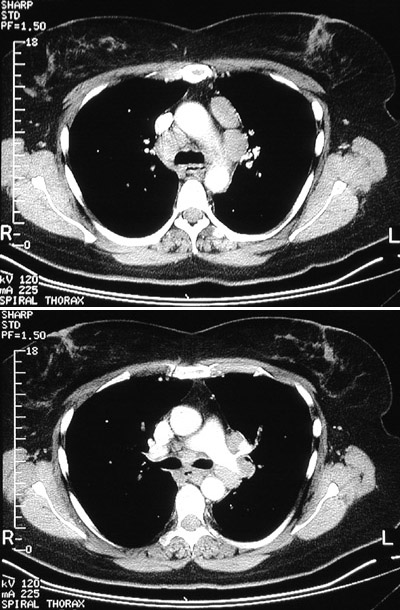

The CT panels seen here with "bone" window setting illustrate prominent lymphadenopathy in a middle aged woman with sarcoidosis. Lymph node involvement is seen in 100% of cases of sarcoidosis, and the hilar nodes are most often involved.